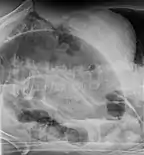

Coffee bean sign in a person with sigmoid volvulus

Coronal view of sigmoid volvulus with "whirlpool sign"